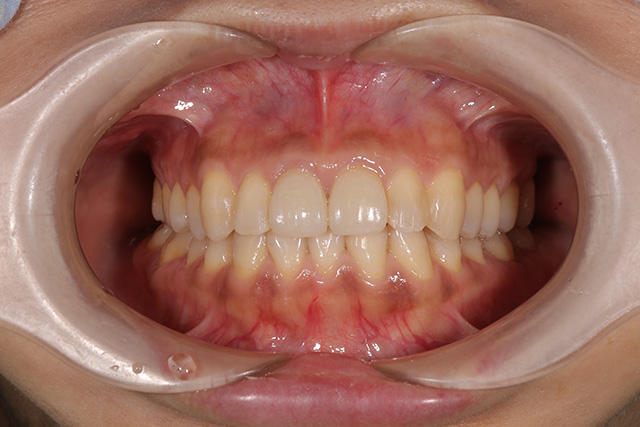

審美症例